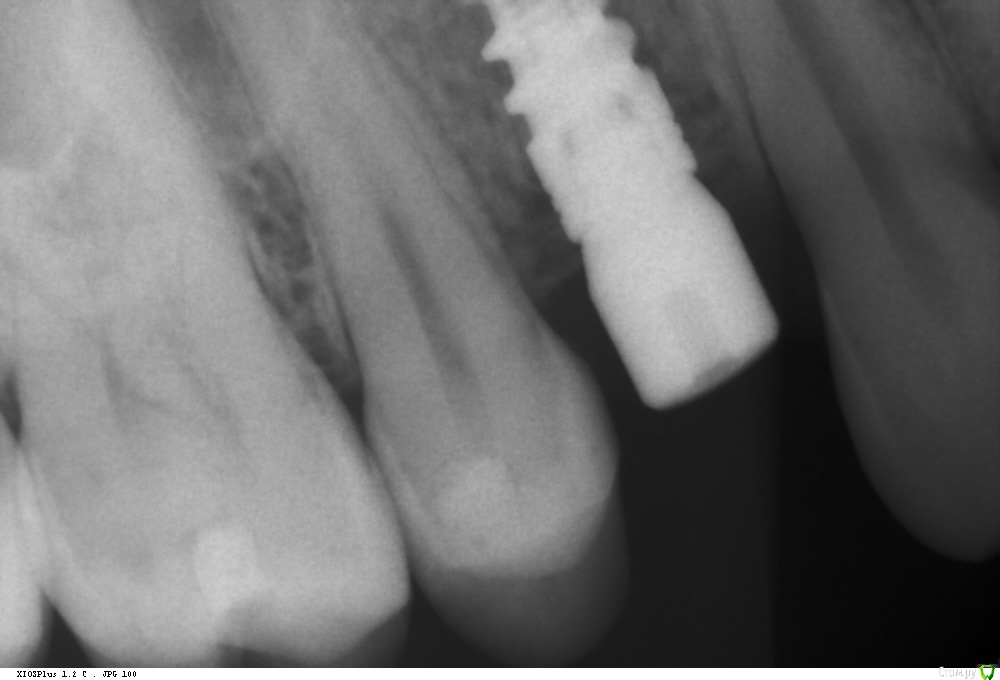

Ponchik Опубликовано 1 августа, 2017 Автор Поделиться Опубликовано 1 августа, 2017 Так и не состоялся тот случай, но сразу же пришла другая пациентка с подобной проблемой. (Проблема в докторе не делающем синус-лифтинга)Планирование Что получилось сразу Формирователь через 3 месяца Ставил AB SPI 4.2 - 8 Фрезой до 6мм, далее вогнутым остеотомом. Изменений в звуке не заметил. Достучал до ограничителя и все.Что в пазухе проблемы увидел, только потом на КТ после имплантации.Всё.Кидайте тапками.P.S.Это был первый имплант на верхней челюсти. Ссылка на комментарий

kamranchick Опубликовано 1 августа, 2017 Поделиться Опубликовано 1 августа, 2017 Так и не состоялся тот случай, но сразу же пришла другая пациентка с подобной проблемой. (Проблема в докторе не делающем синус-лифтинга)Планированиедо.jpg Что получилось сразупосле.jpg Формирователь через 3 месяца 3ме.jpg3мес.jpg Ставил AB SPI 4.2 - 8 Фрезой до 6мм, далее вогнутым остеотомом. Изменений в звуке не заметил. Достучал до ограничителя и все.Что в пазухе проблемы увидел, только потом на КТ после имплантации.Всё.Кидайте тапками.P.S.Это был первый имплант на верхней челюсти.если жалоб нет то все ок Ссылка на комментарий